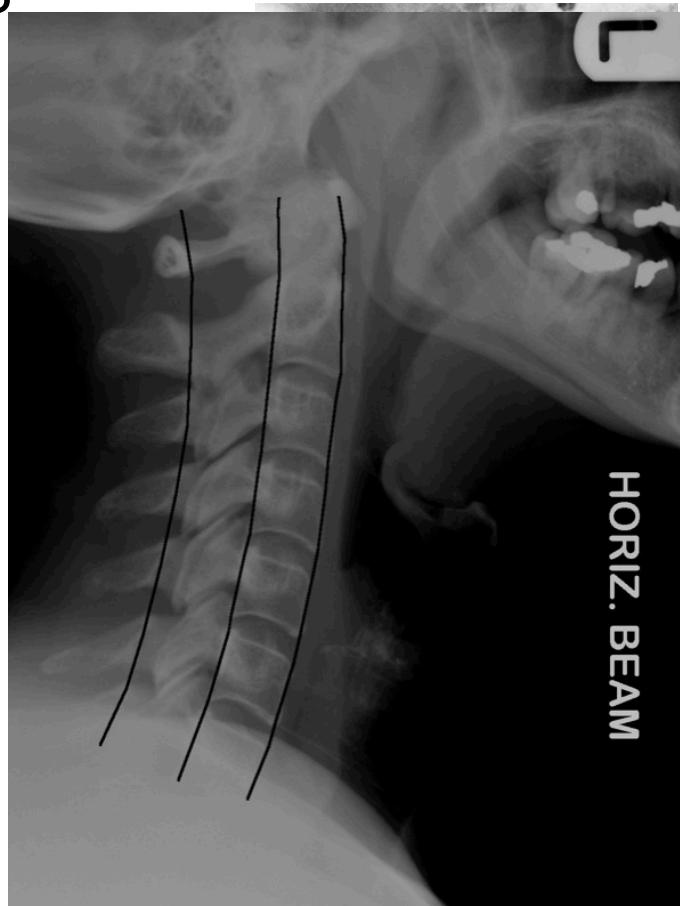

Lateral View:

- All C-vertebrae & upper T1

- Prevertebral soft tissue width

- Four parallel curves:

- Front of vertebral bodies

- Back of vertebral bodies

- Posterior borders of lateral masses

- Bases of spinous processes